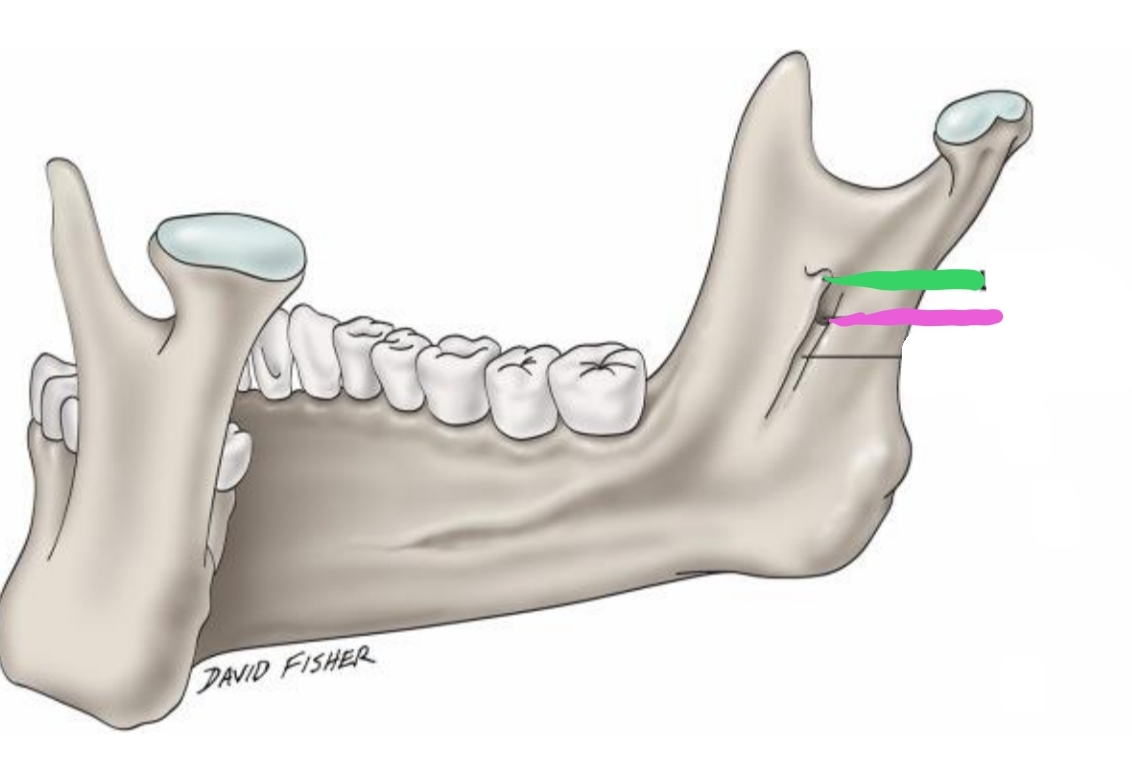

The _________(green) is located on inner surface of ramus; elevation of bone which protects entrance of _________(pink) (opening)

Lingula, mandibular foramen